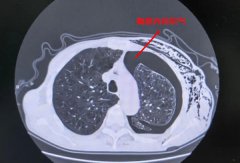

【精准“导航”+无痛定位】南通六院胸外科黑科技让“刁钻”肺结节无处可藏!

肺结节位置太深、藏在骨头缝里? 传统定位又疼又有辐射? 别担心!南通六院胸外科黑科技 CT三维数据融合式经皮穿刺导航定位术 2分钟精准锁定病灶,...